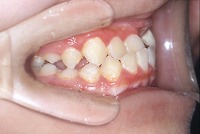

反対咬合と前歯が生えてこない事を主訴に来院された、10歳4か月の男の子です。診断「下顎骨の過成長による骨格性反対咬合で上顎正中の左方偏位と埋伏歯を伴う」1期治療で反対咬合の解消と埋まっていた前歯を牽引しました。